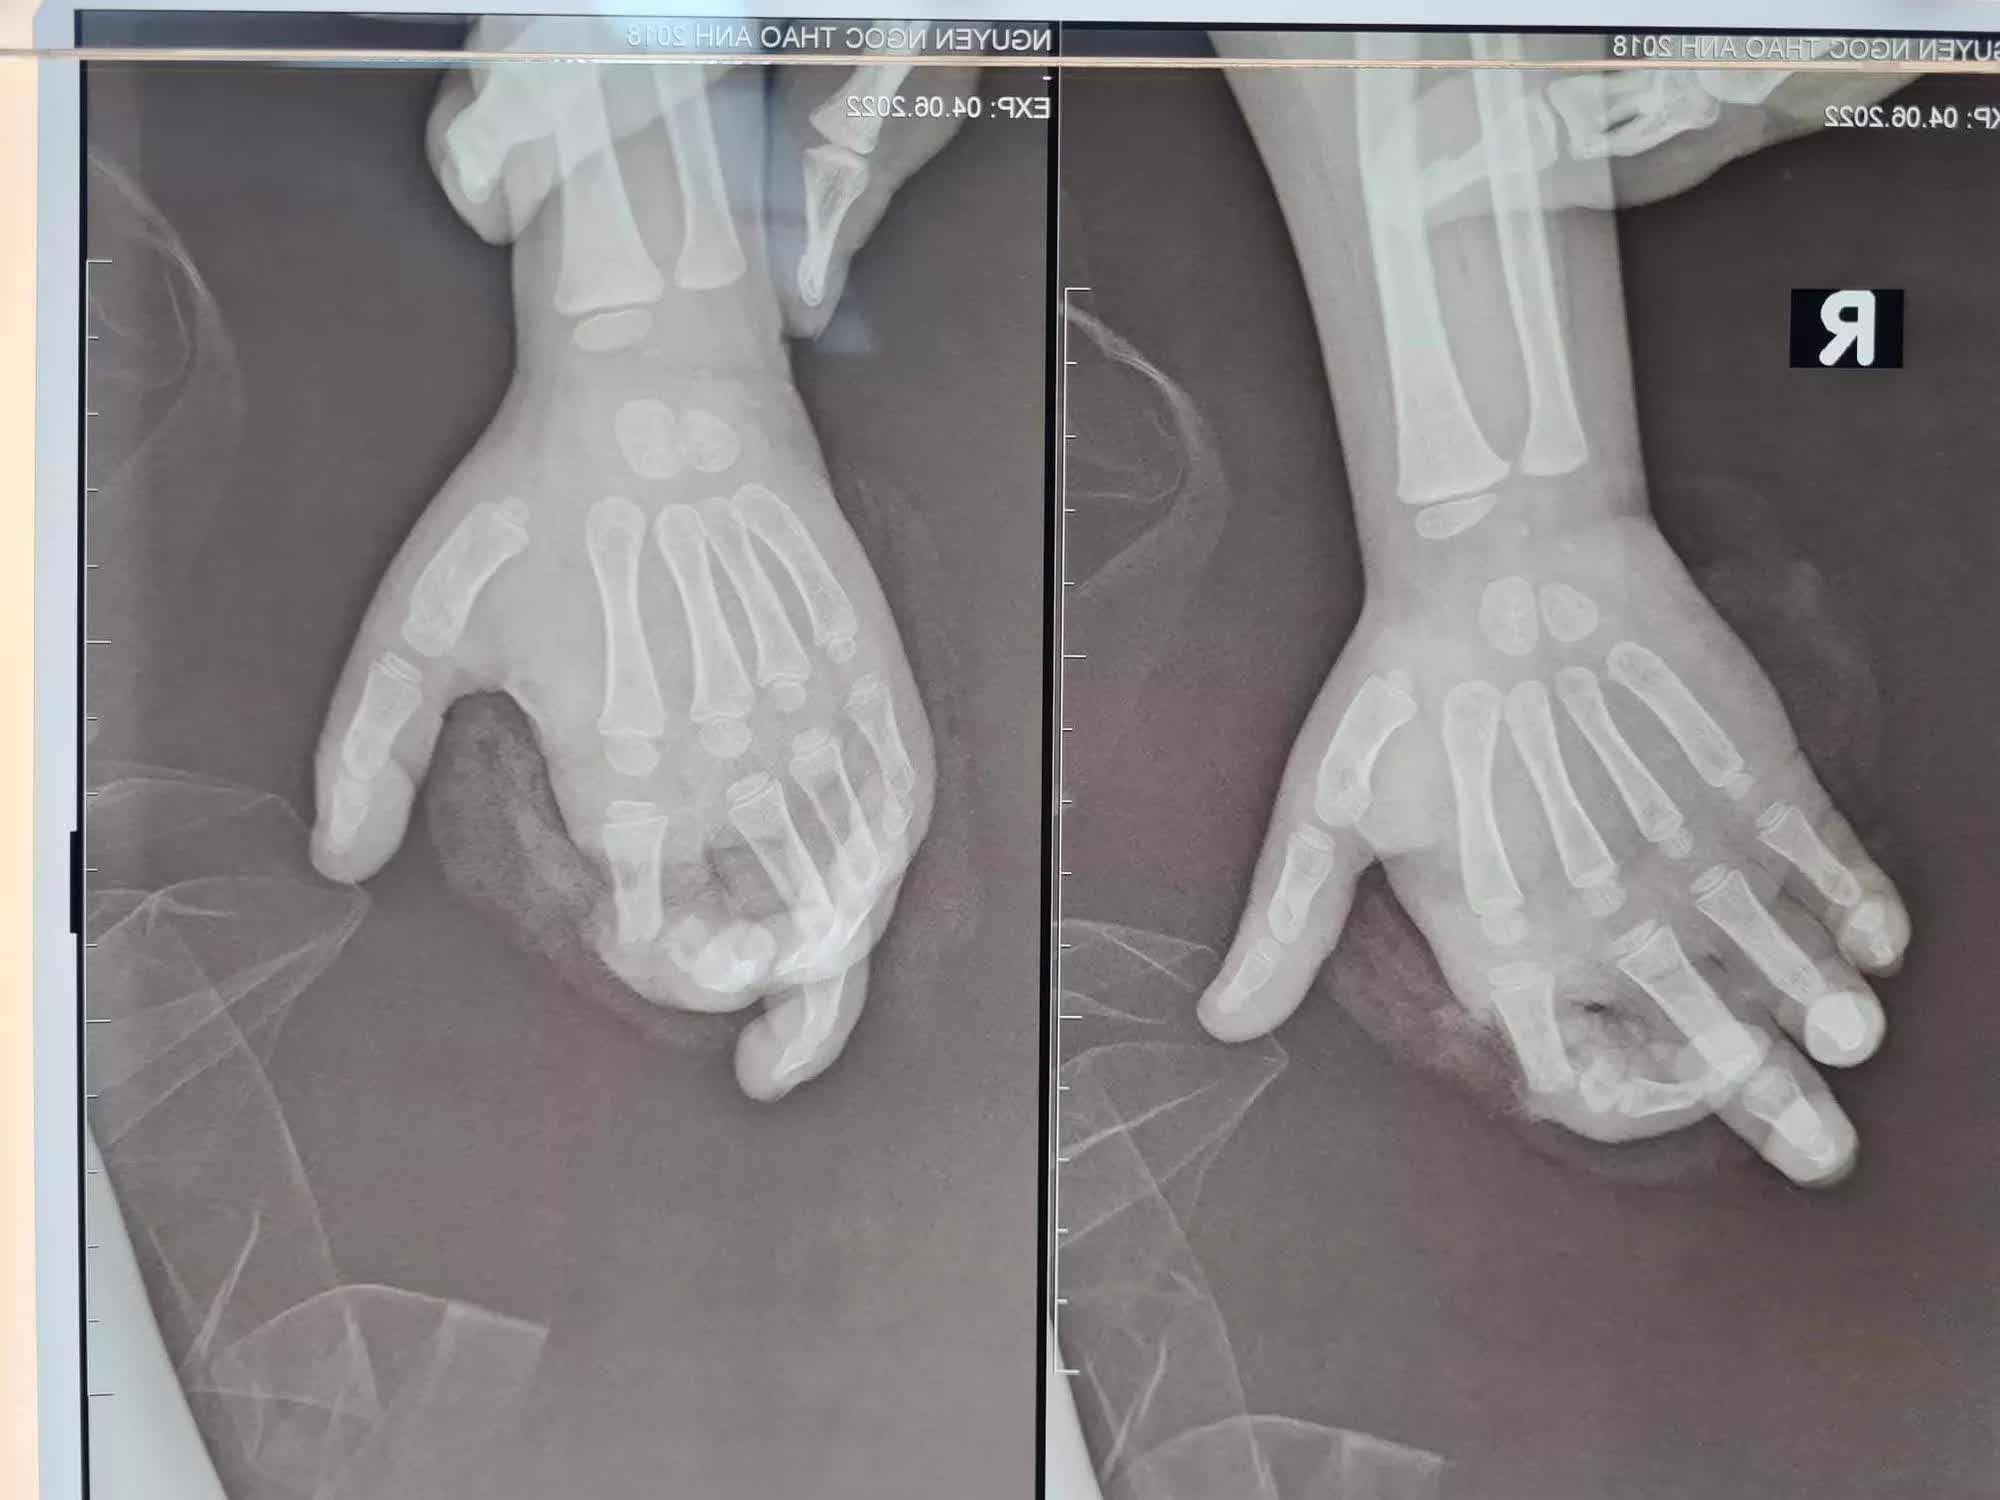

Phim chụp Xquang bé T.A bị nghiền nát ngón 2 do máy xay sinh tố

Sau tai nạn, bệnh nhi bị đứt gần rời ngón 2 tay phải (ngón 2 tay phải chỉ còn dính lại gân gấp), phần ngón đứt gần rời lủng lẳng, trắng bệch do không được cấp máu.